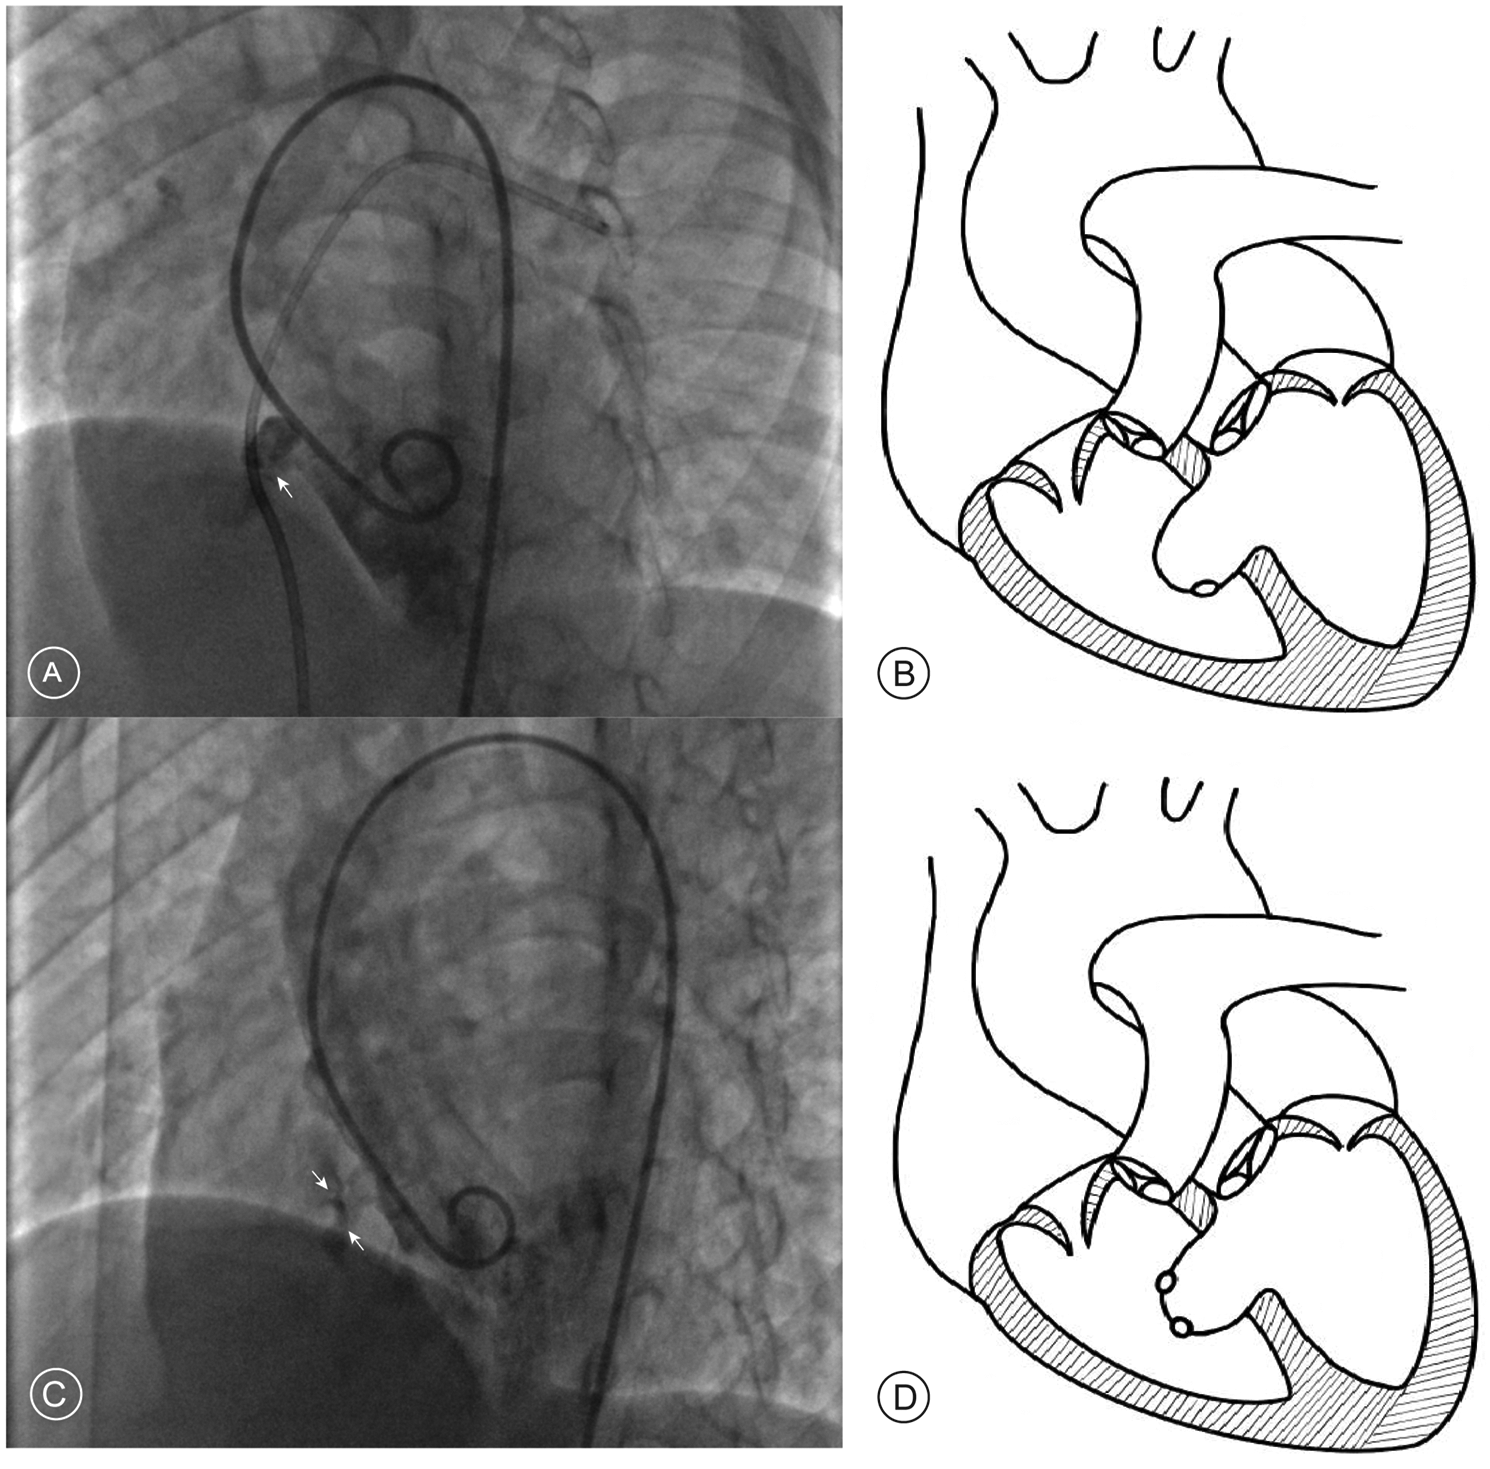

The management of aneurysmal pmVSDs requires specialized consideration, as the aneurysmal morphology fundamentally alters the defect's three-dimensional geometry. This creates complex configurations that can render standard transvenous approaches challenging. For instance, in saccular aneurysms with an acute angle at the right ventricular opening, anterograde systems struggle to achieve proper alignment, a difficulty the retrograde approach accommodates more easily (Figures 1A,B). In cases of multi-fenestrated or “sieve-like” aneurysms, the retrograde route allows for superior device manipulation to ensure the left disc completely covers the septal base, preventing residual shunting (Figures 1C,D). Furthermore, the retrograde approach provides a more direct pathway through tortuous, tunnel-type defects and critically avoids the risk of entangling the tricuspid valve apparatus when adhesions are present.

Figure 1

Angiographic findings and schematic diagrams of aneurysmal pmVSD. (A) Left ventriculogram in a long-axis oblique view showing a saccular aneurysm where the exit to the right ventricle forms an acute angle (white arrow). (B) Corresponding schematic diagram illustrating the acute angle. (C) Left ventriculogram showing a multi-fenestrated or “sieve-like” aneurysm, identified by multiple small contrast jets exiting into the right ventricle (white arrows). (D) Corresponding schematic diagram of a multi-fenestrated aneurysm.